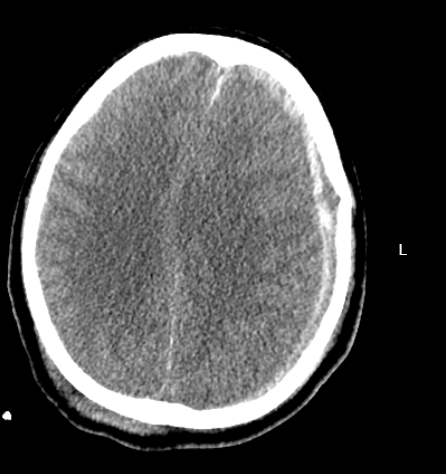

近日,绍兴袍江医院急诊科紧急接收了一名由120转运来的意识不清危重患者。经快速检查,患者被确诊为创伤性枕部跨窦硬膜外血肿、创伤性蛛网膜下腔出血、左侧额颞部硬膜下血肿,同时合并全身多处损伤,病情危急。

该患者所受损伤为颅脑“对冲伤”,即头部前后方同时受力受损,是多发伤中的常见类型。更棘手的是,患者合并小脑创伤——这一创伤类型在所有颅脑创伤中占比仅2%-5%,临床处理难度极大。

患者入院后病情迅速恶化,半小时内即陷入深昏迷状态,呼之不应且对强刺激无任何反应。卒中中心立即启动多学科联动急救机制,将患者紧急推送至手术室,抢救随即展开。

复查显示,患者左侧额颞部硬膜下血肿体积显著增加,大脑受压情况加剧,生命再次受到威胁。医疗团队当机立断,立即实施第二场手术。